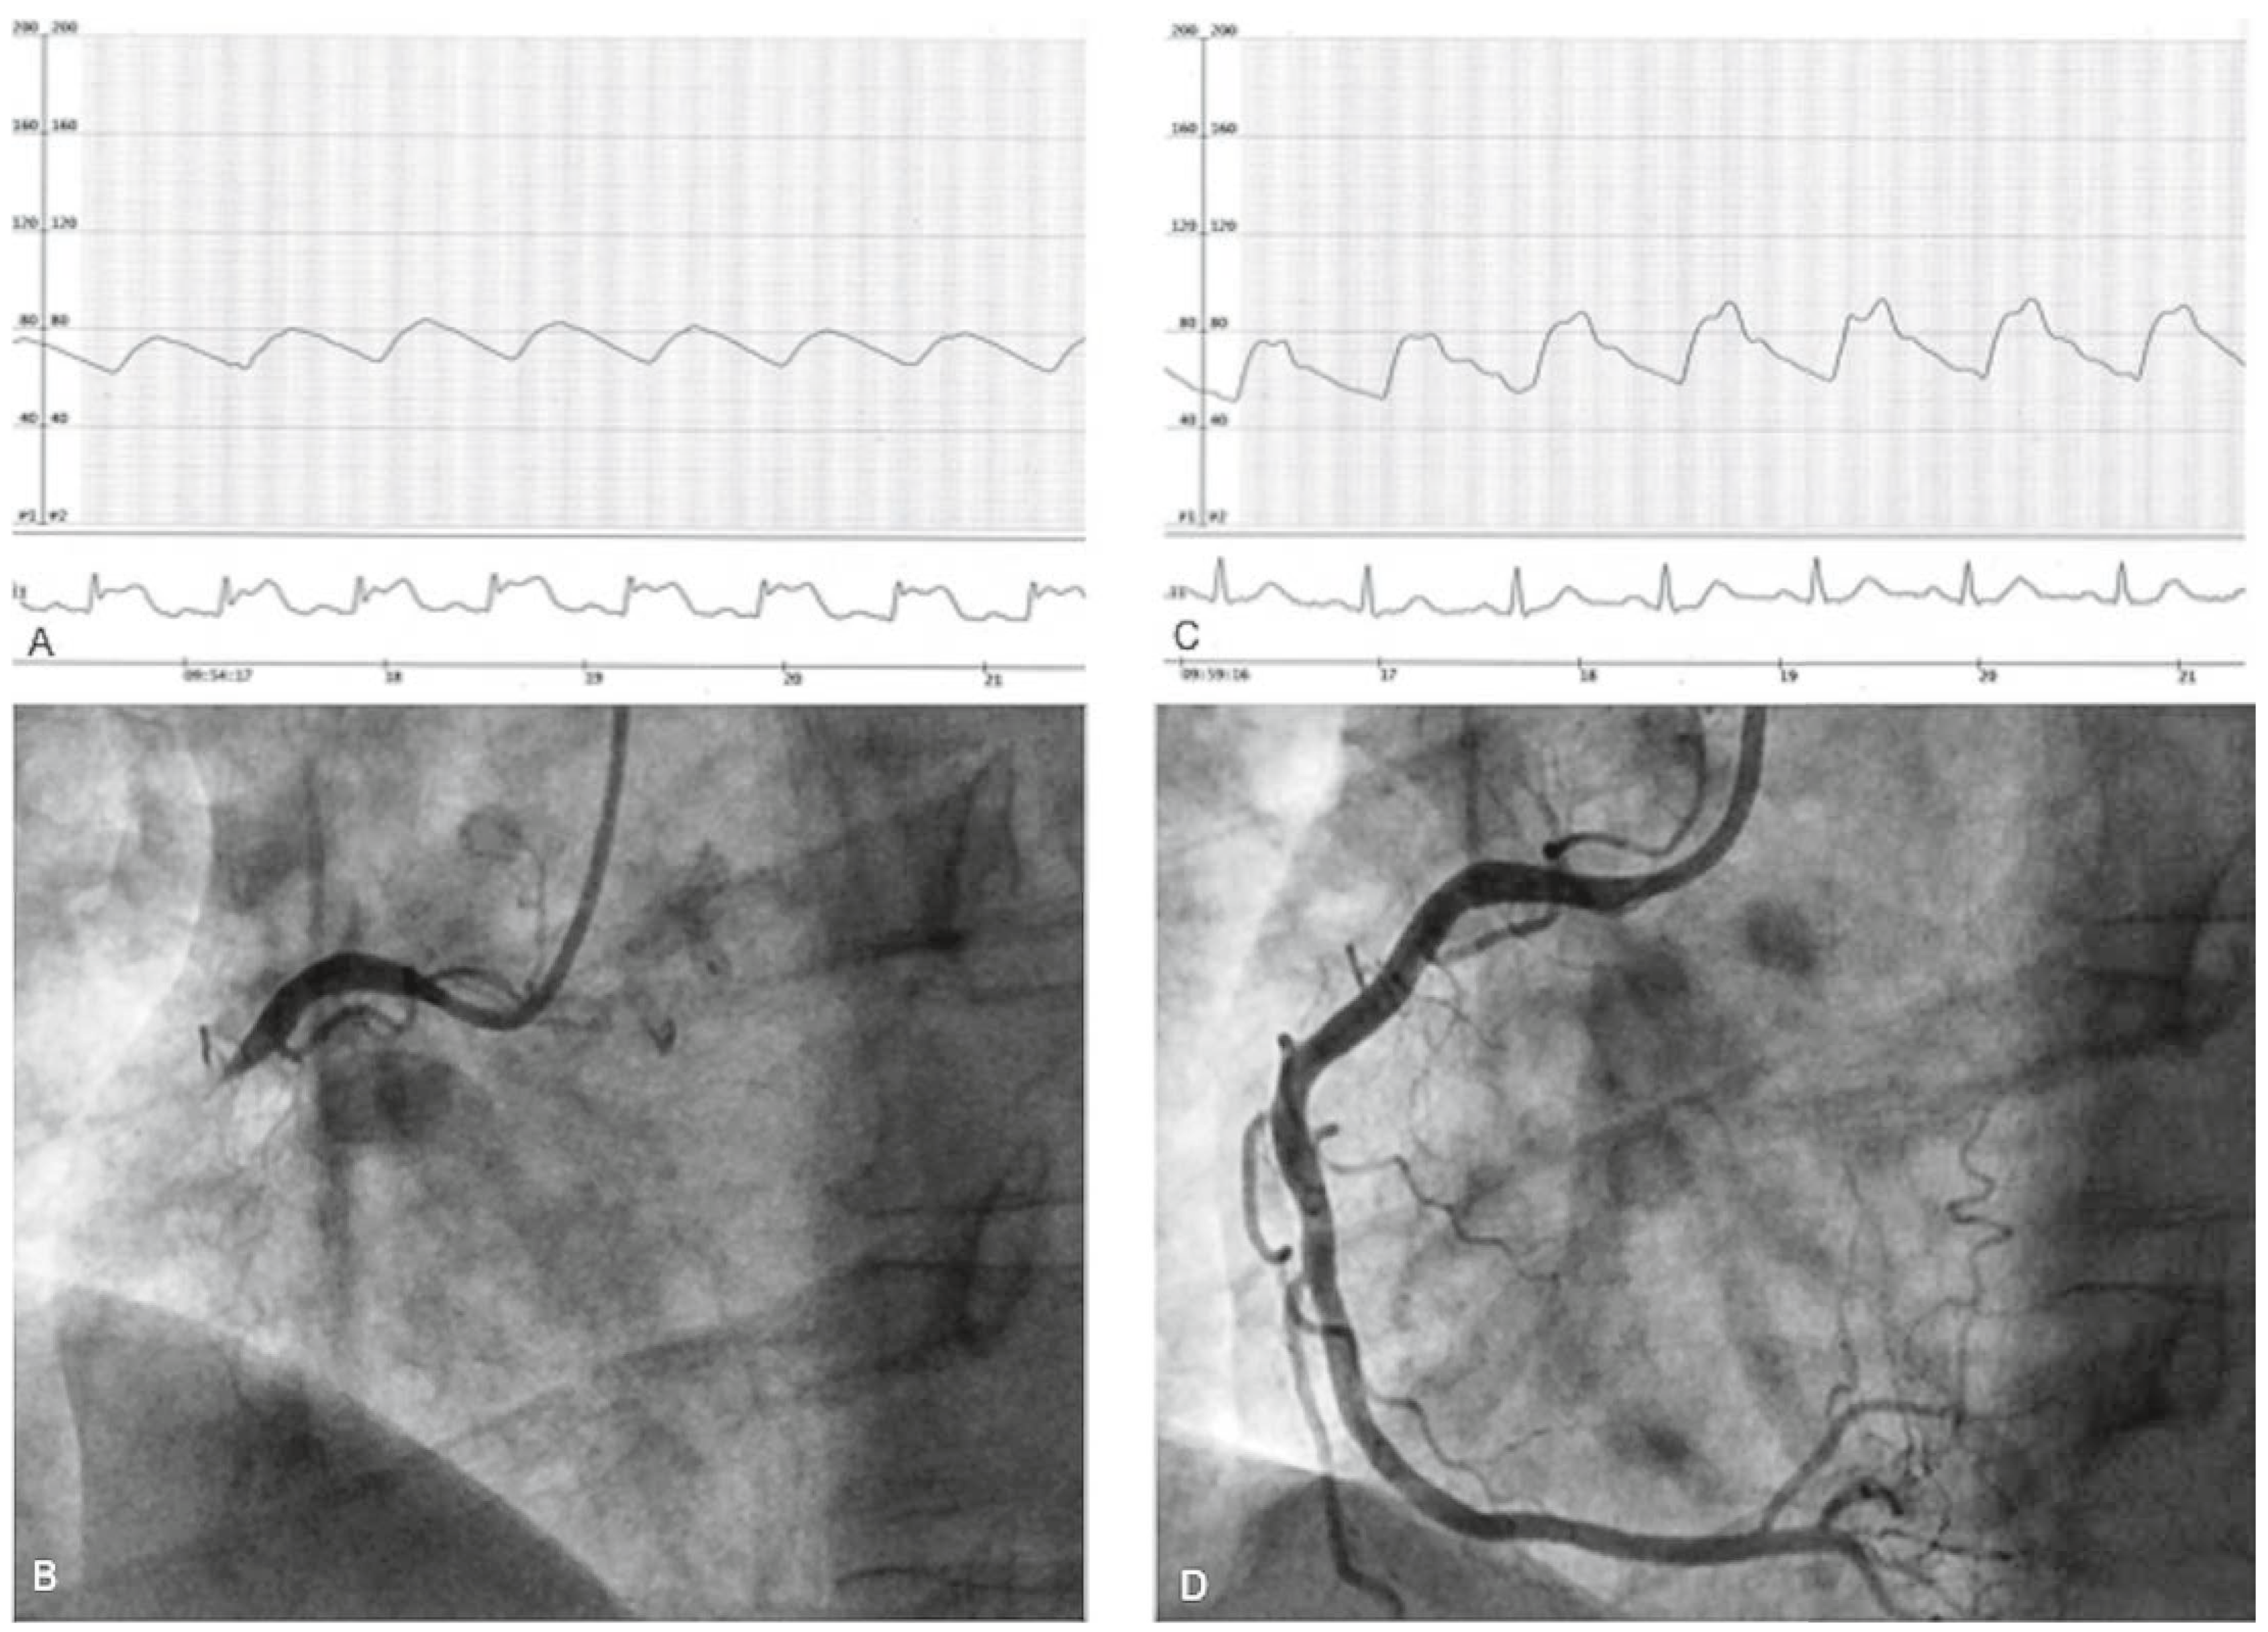

A 50-year-old man, hypertensive and an active smoker, had for many years been complaining of typical chest pain, which occurred most often upon wakening in the morning. Recently prescribed sublingual nitrate relieved the chest pain. Coronary angiography was performed at 9:00 a.m. via a right transradial approach and with 5 Fr diagnostic catheters (Judkins left 3.5 and Judkins right 4.0). At the end of straightforward left coronary injections, which did not show significant coronary stenosis, he experienced his usual intense chest pain with major ST-segment elevation on the monitor (Figure 1A) and subsequent transient complete atrioventricular block. Prompt injection of the right coronary artery (RCA) showed a proximal occlusion (Figure 1B). After sublingual nitrate administration, chest pain progressively disappeared, the ECG normalised (Figure 1C) and the RCA was again open without any significant stenosis (Figure 1D). A daily calcium antagonist was prescribed with sublingual nitrate as needed. Smoking cessation was highly recommended. At the 18-month follow-up the patient was no longer a smoker and still free of cardiac symptoms under chronic medication.

Figure 1. Explanation in text.